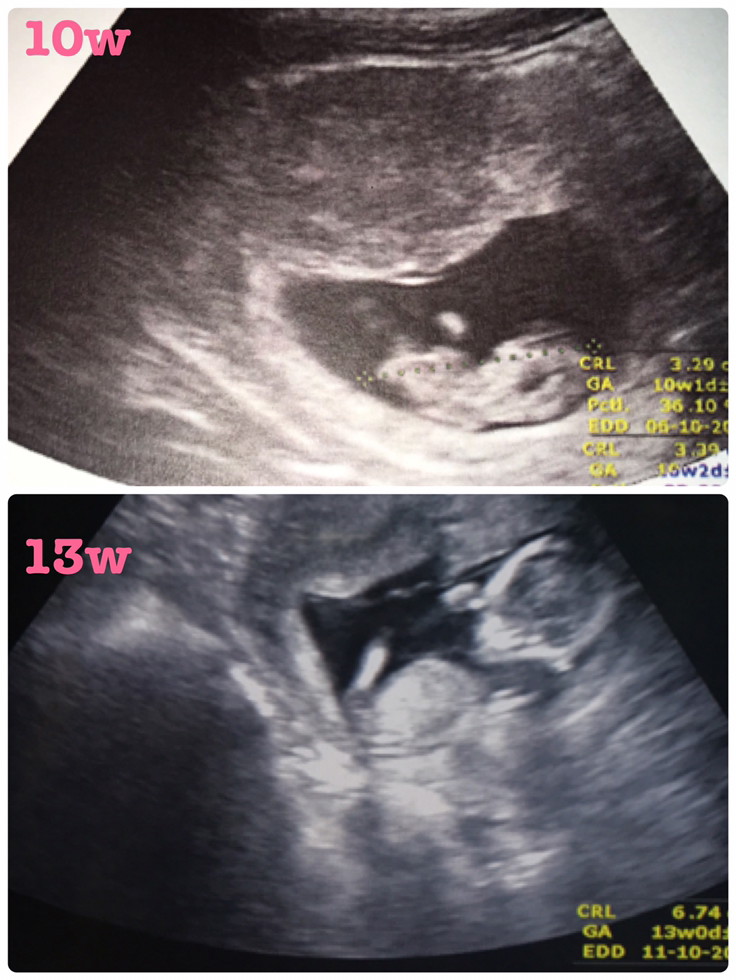

แม่ๆคนไหนมีภาพอัลตร้าซาวด์ประมาณ13วีคบ้างคะ ของเรา13วีค ภาพแบบนี้ค่ะ ดูไม่ออกเลย?

13wค่ะ

10วีค